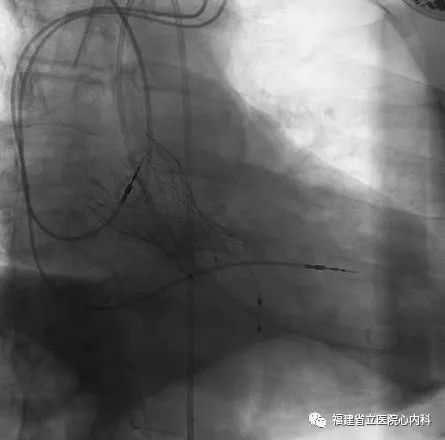

病例4

该病例是三叶瓣,中度钙化,法式窦结构可,但是左冠状动脉开口低,左冠瓣瓣叶冗长,预测掀起的瓣叶可能超过冠脉开口上缘,术者在术前通过CT精准评估冠脉风险,制定详尽的介入治疗策略,术中通过25号球囊预扩进一步确认冠脉情况,最后将29号瓣膜精准植入预期位置,避免冠脉风险,达到预期手术效果。

瓣环

窦部

左冠高度:8.2mm

瓣叶长度:14.9mm

球囊预扩张

植入L29瓣膜